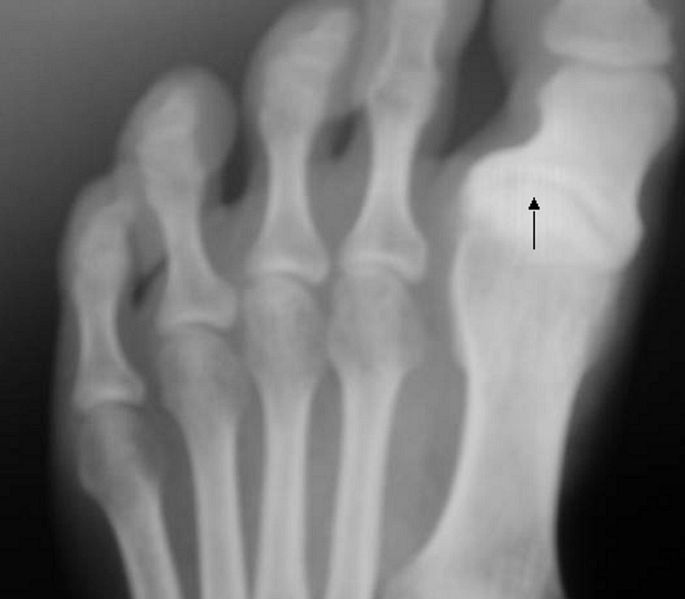

Hallux varus in X-ray

Hallux varus is a deformity of the great toe joint where the hallux is deviated medially (towards the midline of the body) away from the first metatarsal bone. The hallux usually moves in the transverse plane.

The condition has various degrees ..............